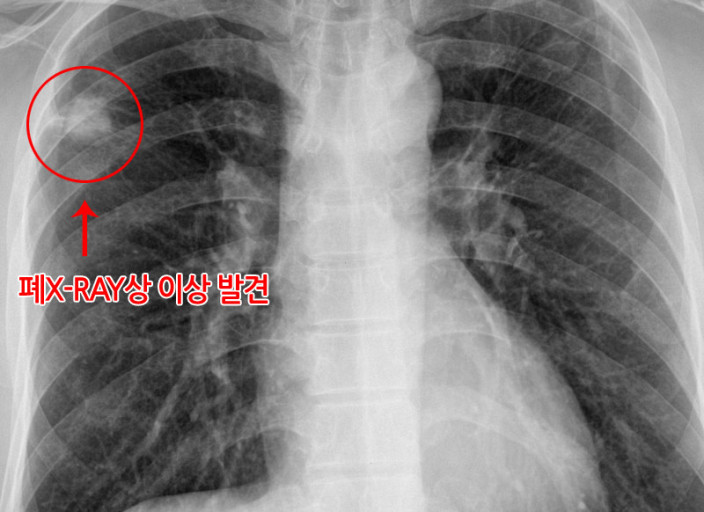

폐암은 위암, 갑상선암 다음으로 3번째로 발병 빈도가 높은 3대 암 중 한 가지입니다. 폐암은 재발과 전이까지의 빈도도 잦은지라 완치가 어렵다고 하며 폐암 발병 초기에는 거의 증상이 없을 수가 있어 수술이 불가능한 3기, 혹은 4기에 주로 진단된다고 합니다.